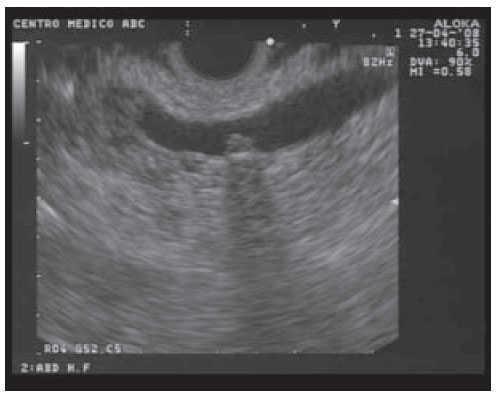

CaseA 58 year-old female was admitted with acute abdominal pain. Abdominal ultrasound reported chronic cholecystitis, cholelithiasis and intra and extra hepatic bile duct dilation; Common bile duct (CBD) measured 9 mm. Liver function tests were within normal range. A cholangio-MRI showed dilated CBD and images suggestive of choledocolithiasis. A laparoscopic cholecystectomy was scheduled. Prior to surgery the patient underwent an ERCP. During the endoscopic procedure the papilla was localized within a duodenal diverticulum. After several attempts the bile duct could not be accessed; the pancreatic duct was cannulated several times instead; a single flap pancreatic stent was placed and the procedure was aborted. The day after, a EUS exam using a linear array echoendoscope (GF-UC140P-AL5;Olympus) showed a dilated CBD measuring up to 9 mm as well as a single stone within its distal portion. (Figure 1)

Figure 1. Endoscopic ultrasound image from the second portion of the duodenum showing a small biliary stone within the common bile duct.